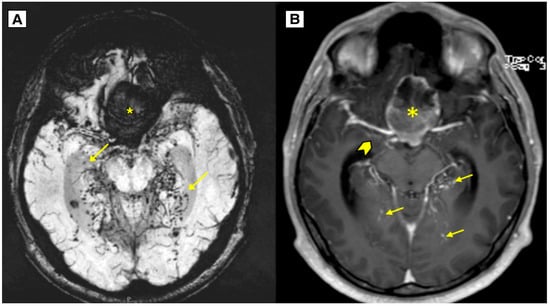

2.2. Imaging Findings